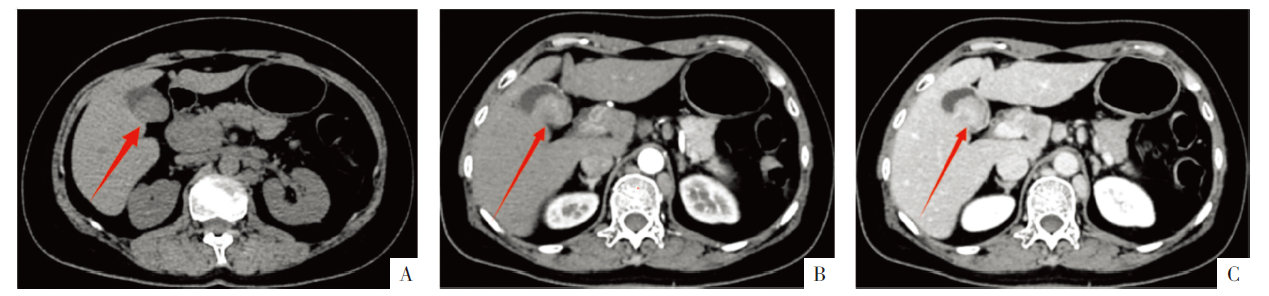

• 图2 胆囊病变的CT影像。A图为平扫CT,B、C图分别为增强CT动脉期和静脉期影像。箭头示胆囊病灶。